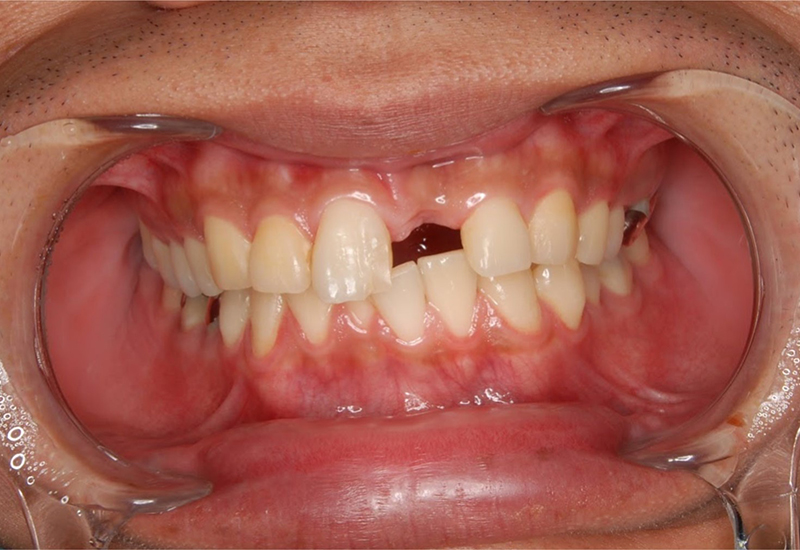

前歯の怪我:インプラント・ジルコニア症例

友人と喧嘩になり、上顎前歯部(左上1)を破折。 |

治療前 |

治療前